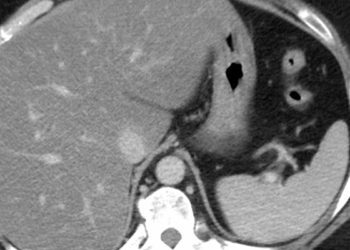

Durvalumab and bevacizumab plus chemoembolization improves progression-free survival in hepatocellular carcinoma

1. Progression-free survival was significantly greater in the durvalumab plus bevacizumab group compared to placebo. 2. Common treatment-related adverse events ...